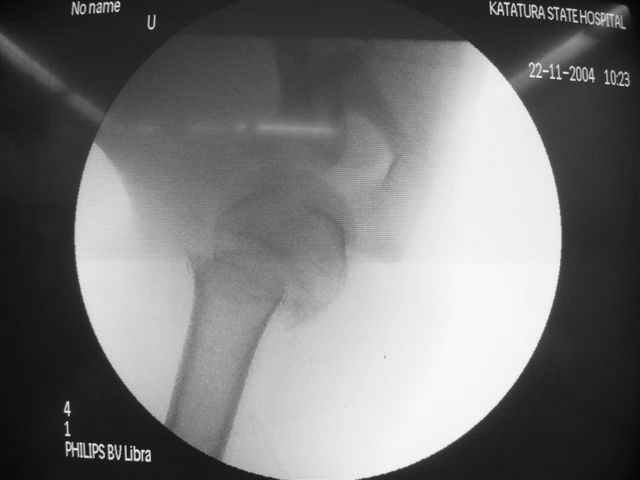

Перелом шейки плеча

Коллеги, Больной прооперирован вчера. 19 летний пациент с переломом шейки плеча. Закрытая репозиция и чрескожная фиксация спицами под контролем ЭОПа ( техника проф. Лазарева)

Интраоперационный контроль на стабильность фиксации - сомнений в стабильности фиксации не возникло. Послеоперационный контроль сегодня......

Необходимость послеоперационного Рг контроля..... Больной запланирован на повторную манипуляцию и транспозицию спиц Евгений И Чекашкин